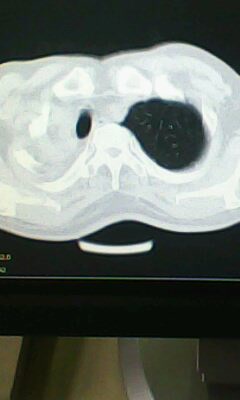

标题: CT25675:男 71 肺癌部分切除术后 3年 [打印本页]

标题: CT25675:男 71 肺癌部分切除术后 3年

两肺感染性病变\\右侧胸膜增厚

术后改变,双肺内纤维索条影考虑与放疗有关。